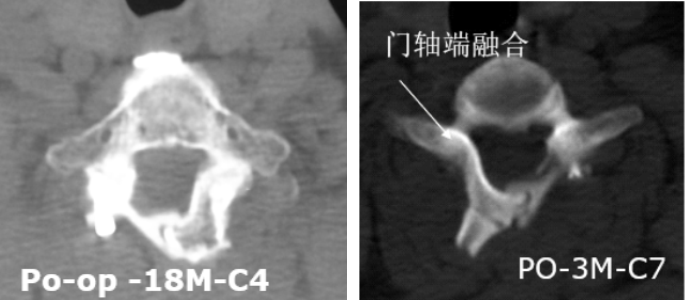

1.最大限度保留并重建后方结构

3.有效防止术后再关门,为脊髓提供强力保护

4.可融合,远期稳定性好